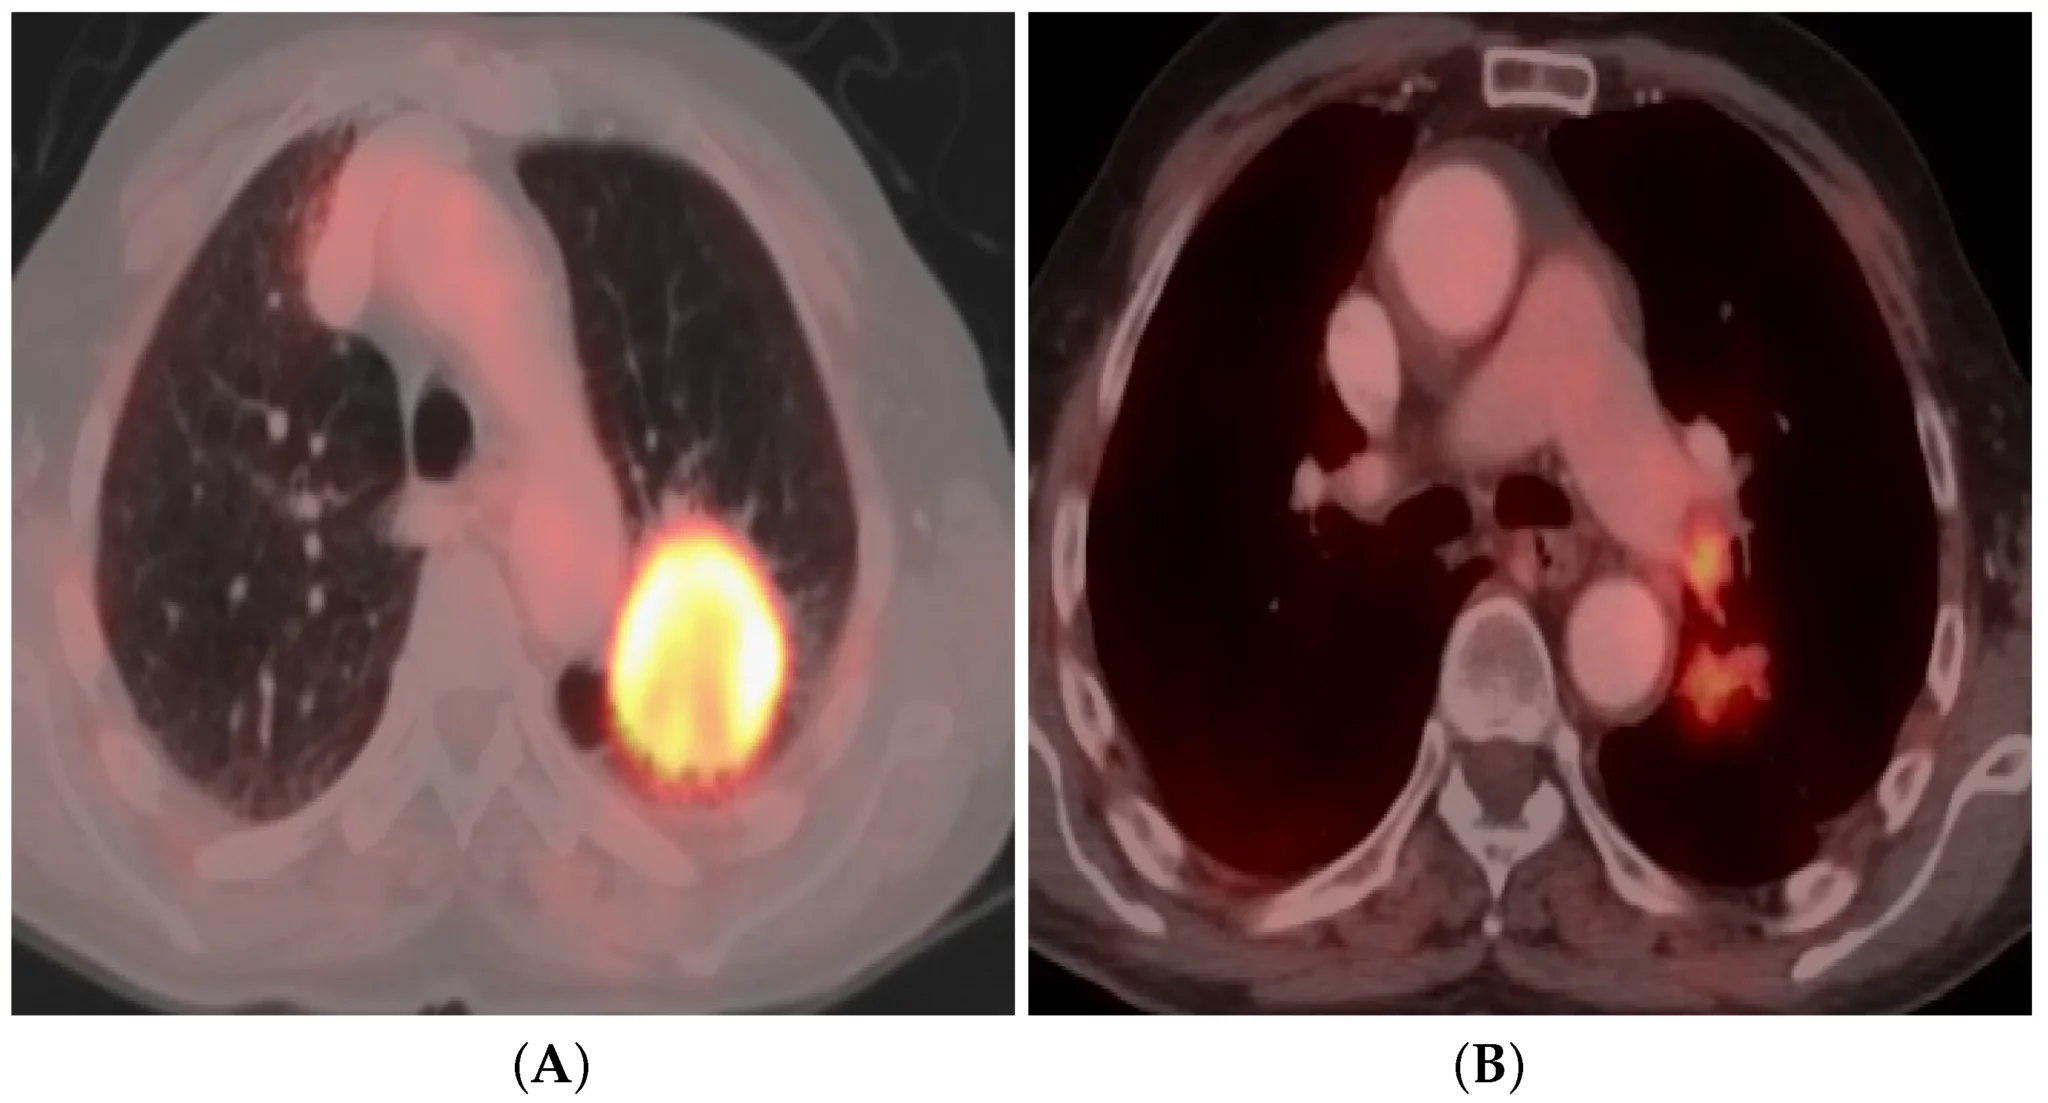

2. Lung Cancer: Imaging and Staging by Dr. Tany Chandra

Dr. Tany Chandra discusses the crucial role of imaging in the diagnosis and staging of lung cancer—a must-know topic for every radiology resident.

Key Highlights:

• Knowing imaging techniques and staging enables radiologists.

• Accurate clinical recommendations for improved patient care.